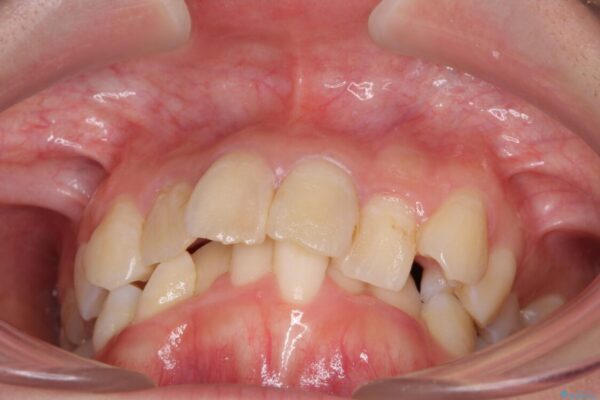

内側に倒れ込んだ歯や下の前歯が隠れてしまうほどの咬み合わせを改善したいとのことで来院された患者様です。

治療前

• デコボコと深い咬み合わせ ワイヤー装置での抜歯矯正 治療前画像